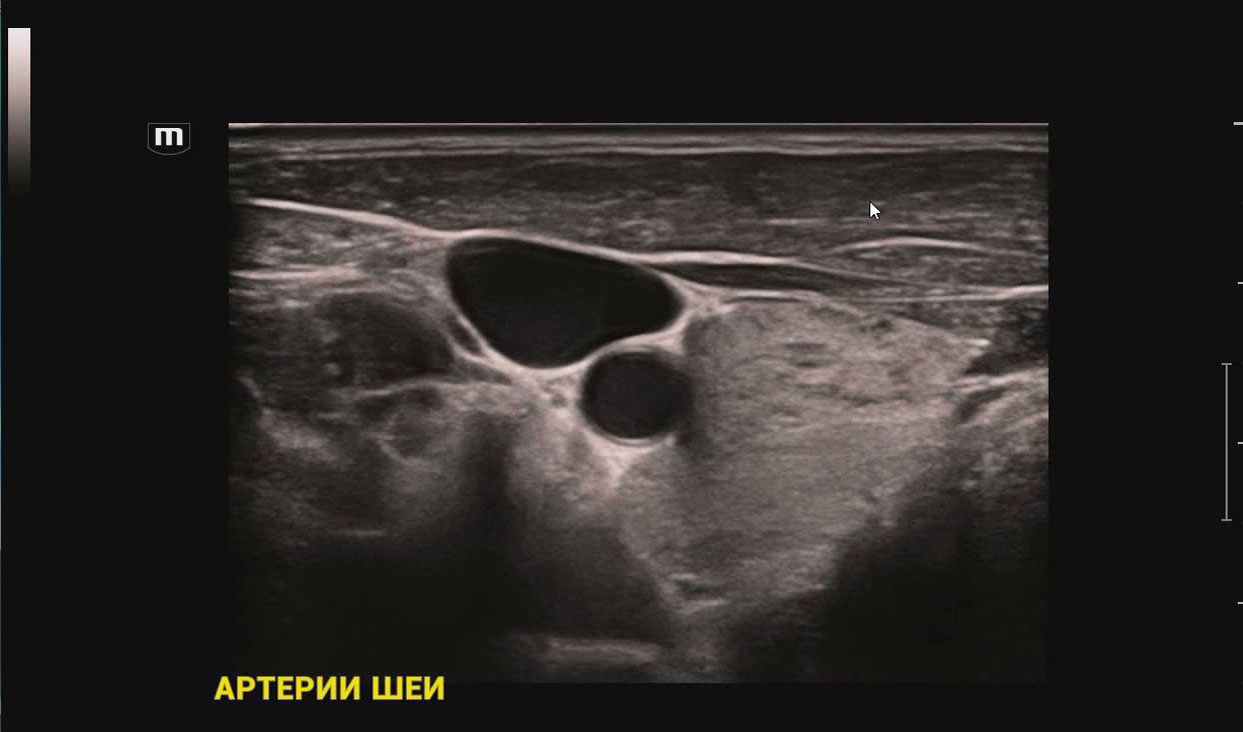

SmartTrack SmartTrack - это технология для сосудистых исследований от Mindray, которая позволяет сократить повторяющиеся и отнимающие много времени шаги во время исследования. Функция автоматически позиционирует допплеровскую рамку и изменяет угол ее наклона в режиме ЦДК, определяет положение и размер контрольного объема в режиме PW.

Auto IMT Автоматическая детекция и вычисление толщины комплекса интима-медиа сонной артерии. Опция Auto IMT позволяет получить точную и эффективную оценку состояния стенки сонной артерии.

V-Flow В технологии V-Flow используются цветные вектора для кодирования скорости и направления движения клеток крови. Благодаря ультравысокой частоте кадров, обеспечивается чрезвычайно показательная, точная и не зависящая от угла визуализация сложных сосудистых гемодинамических показателей.